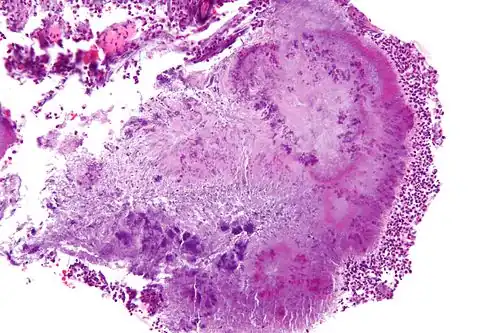

Micrograph of actinomycosis, H&E stain -